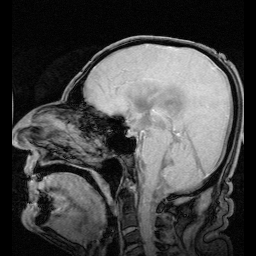

التشخيص

يعتمد التشخيص على التاريخ المرضي والفحص السريري، ومعرفة الحالة المصاحبة، بالإضافة إلى بعض الفحوصات الإشعاعية مثل :

- الأشعة المقطعية : وتعطي صور واضحة عن الحالة ومكان الانسداد.

- الأشعة فوق الصوتية : وتعطي صورة عن تطور حجم البطين وتستخدم في المتابعة.